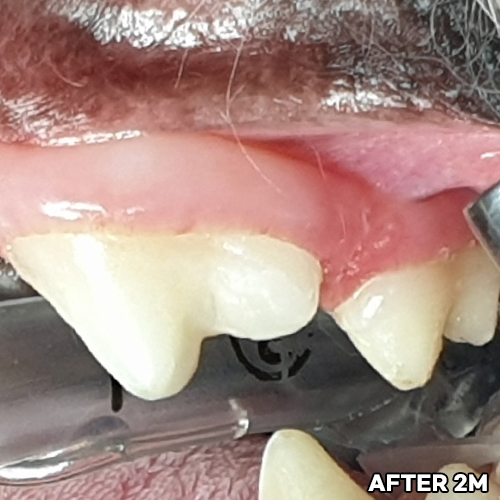

치아뿌리까지 파절된 강아지어금니 빨갛게 부어오른 잇몸치료~ 2년 뒤에 재생된 잇몸뼈 CT로 확인! 모든 동물병원에서 발치하자고 했지만 힐링힐스동물치과병원에서 되살려진 어금니!